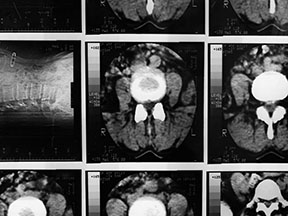

• Radiology / Diagnostics

It is crucial to correctly identify the causes of pain to succesfully manage pain. ALLEGIANT utilizes the latest technological advances in diagnostic imaging and protocols.